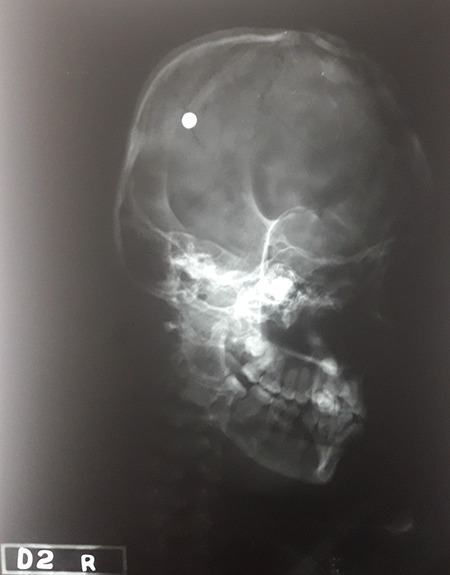

HEADSHOT AUTOPSY

Fig 1: Large irregular and deep laceration on the front of the head.

Fig 2: Deep and irregular laceration on the left side of the top of the head.

Fig 3: Compound fractures under each laceration.

Fig 4: Some of the fragments were not in place in the reconstruction of skull cap.

Fig 5: Radiating fractures extending to the base of skull, from the anterior cranial fossa to the middle cranial fossa, incorporating the sphenoid bone, ethmoid bone, and sella turcica.

Fig 6: A shrapnel found lodged in the mid aspect of its origin—in the rim of the temporal fossa of the skull.

Fig 7: A shrapnel (metal ball measuring 0.5 cm in diameter).

Fig 8: Brain parenchyma showing lacerations on the frontal and parietal lobes.

Fig 9: Multiple underlying contusions on bilateral frontal white matter.

Fig 10: Brain laceration was associated with localized subarachnoid hemorrhage.

Fig 11: Penetrating irregular laceration, running diagonally on the right ear, involving the triangular fossa.

The deceased was a 15-year-old girl who was participating in the Easter mass at St. Sebastian’s Church—Katuwapitya, Negombo—when a suicide bomber entered the church and blew himself up, killing over hundred and injuring and permanently disabling many more. Following the explosion, the mother of the deceased noticed the deceased being rushed to the hospital in a car. However, she was pronounced dead on admission.

Pre autopsy radiology revealed spherical shrapnel in the temporal region (Figure 12). The injuries that are of value in analyzing the injury pattern and those that will help to reconstruct the event are described below, very briefly. The exact dimensions and accurate anatomical locations are not being described.

There was a large irregular and deep laceration on the front of the head ( Figure 1 ), with its midpoint roughly 7 cm above the glabella and another deep and irregular laceration was observed on the left side of the top of the head ( Figure 2 ). The surfaces of the scalp beneath these injuries were severely contused. Under each of these lacerations were compound fractures ( Figure 3 ). Upon reconstruction of the skull cap, some of the fragments were not in place ( Figure 4 ). Few fragments were embedded in the brain parenchyma. The skull bone between the abovementioned compound fractures were also fragmented, therefore for convenience these two fractures are considered as one whole compound fracture. Inner beveling was noticed from 4 o’ clock to 7 o’ clock position and outer beveling was noticed from 12 o’ clock to 2 o’ clock position giving rise to a keyhole lesion. There were radiating fractures from 12 o’ clock, 5 o’ clock, 7 o’ clock, 8 o’ clock, and 10 o’ clock positions. The fracture radiating from the 7 o’ clock position ran downward and inward into the right orbit and toward the base of skull and extending from the anterior cranial fossa to the middle cranial fossa, incorporating the sphenoid bone, ethmoid bone, and sella turcica ( Figure 5 ). The coronal suture intersecting the compound fracture showed features of sutural diastasis.

Internal examination revealed an extensive dural tear underlying the compound fracture. Upon reflection of the right temporalis muscle, a shrapnel (metal ball measuring 0.5 cm in diameter) was found lodged in the mid aspect of its origin—in the rim of the temporal fossa of the skull ( Figures 6 and 7 ). The brain was grossly edematous with brain parenchyma showing lacerations on the frontal and parietal lobes ( Figure 8 ). There were multiple underlying contusions on bilateral frontal white matter ( Figure 9 ). The brain laceration was associated with localized subarachnoid hemorrhage ( Figure 10 ). Small subarachnoid hemorrhage was noted on the basal aspect of the brain.